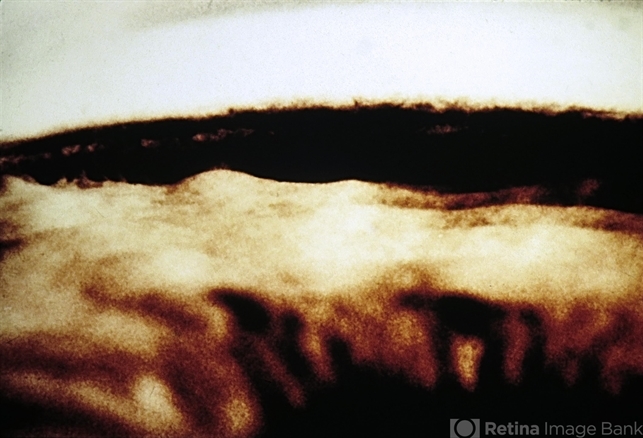

- angle recession

- "Hills and valleys" appearance of postcontusion angle recession.